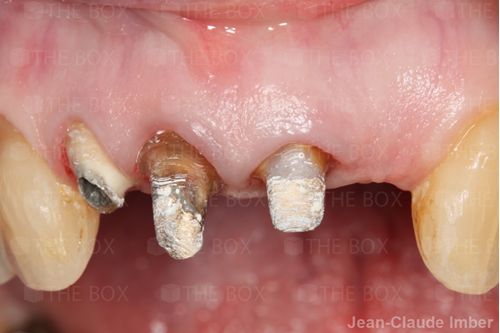

A new case was made public by Jean-Claude Imber check it out here.